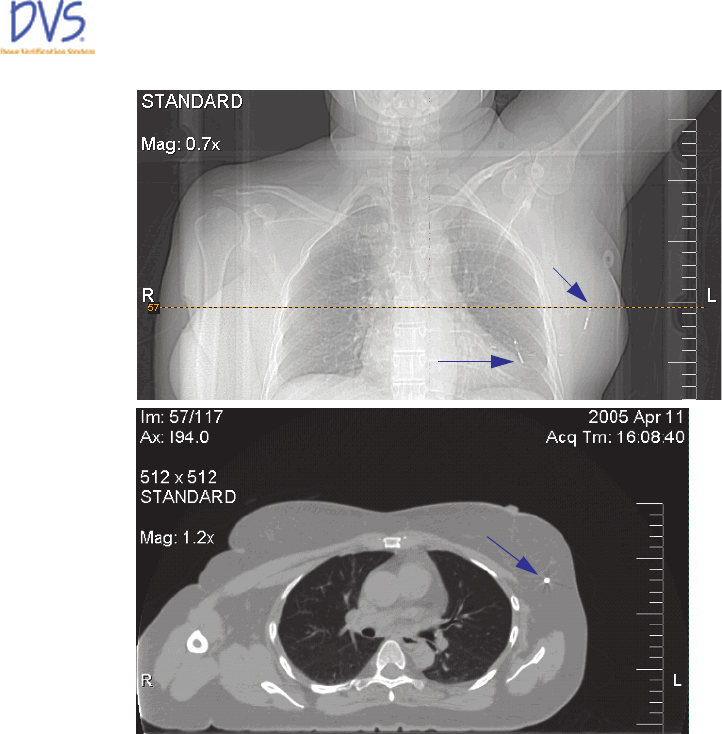

Figure 28 — CT Scout and Transverse Images

Sensitive Volume

Antenna “Flare” End

Sensitive Volume Point

Dose Location